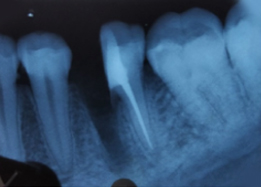

Immediate Post-Surgical IOPAR

Pre-OP IOPAR